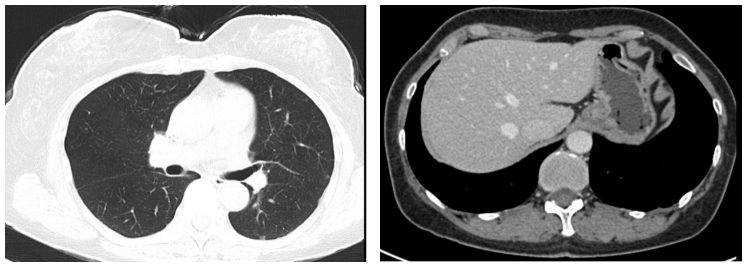

④三线治疗:曲妥珠单抗(汉曲优) 300mg Q3W+吡咯替尼 320mg QD+唑来膦酸4mg Q3M,并予以局部区域放疗。维持治疗至2022.03.31出现新发左肺转移灶及右侧小脑转移灶。行支气管镜检查,并取左肺下叶背段支气管开口见新生物活检,病理提示:(左肺结节)乳腺癌转移,Ki-67(20%,+),ER(-),PR(-),HER2(3+)。右侧小脑异常信号,1.2cm(图5),考虑转移。疗效评价PD,PFS 16个月。

图5. 2022.03左肺及右侧小脑影像图

两个疗程后评估:左肺下叶转移灶较前缩小,1.1cm;右侧小脑转移灶较前缩小,0.8cm(图6)。疗效评价 PR,继续维持该方案。

图6. 2022.05左肺及右侧小脑影像图